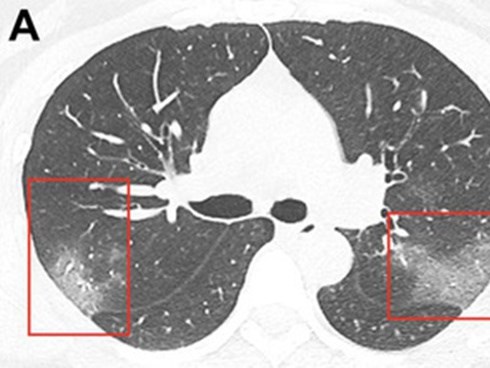

Chụp X-quang phổi cho bệnh nhân 33 tuổi nhiễm virus corona, bác sĩ rùng mình phát hiện hình ảnh tương đồng dịch bệnh trong quá khứ

Nếu không biết về đợt bùng phát này, bạn sẽ đọc bản quét và cho rằng bệnh nhân này bị viêm phổi vì đây là chứng bệnh phổ biến nhất mà chúng ta có thể trông thấy bằng hình ảnh "tổn thương kính mờ".